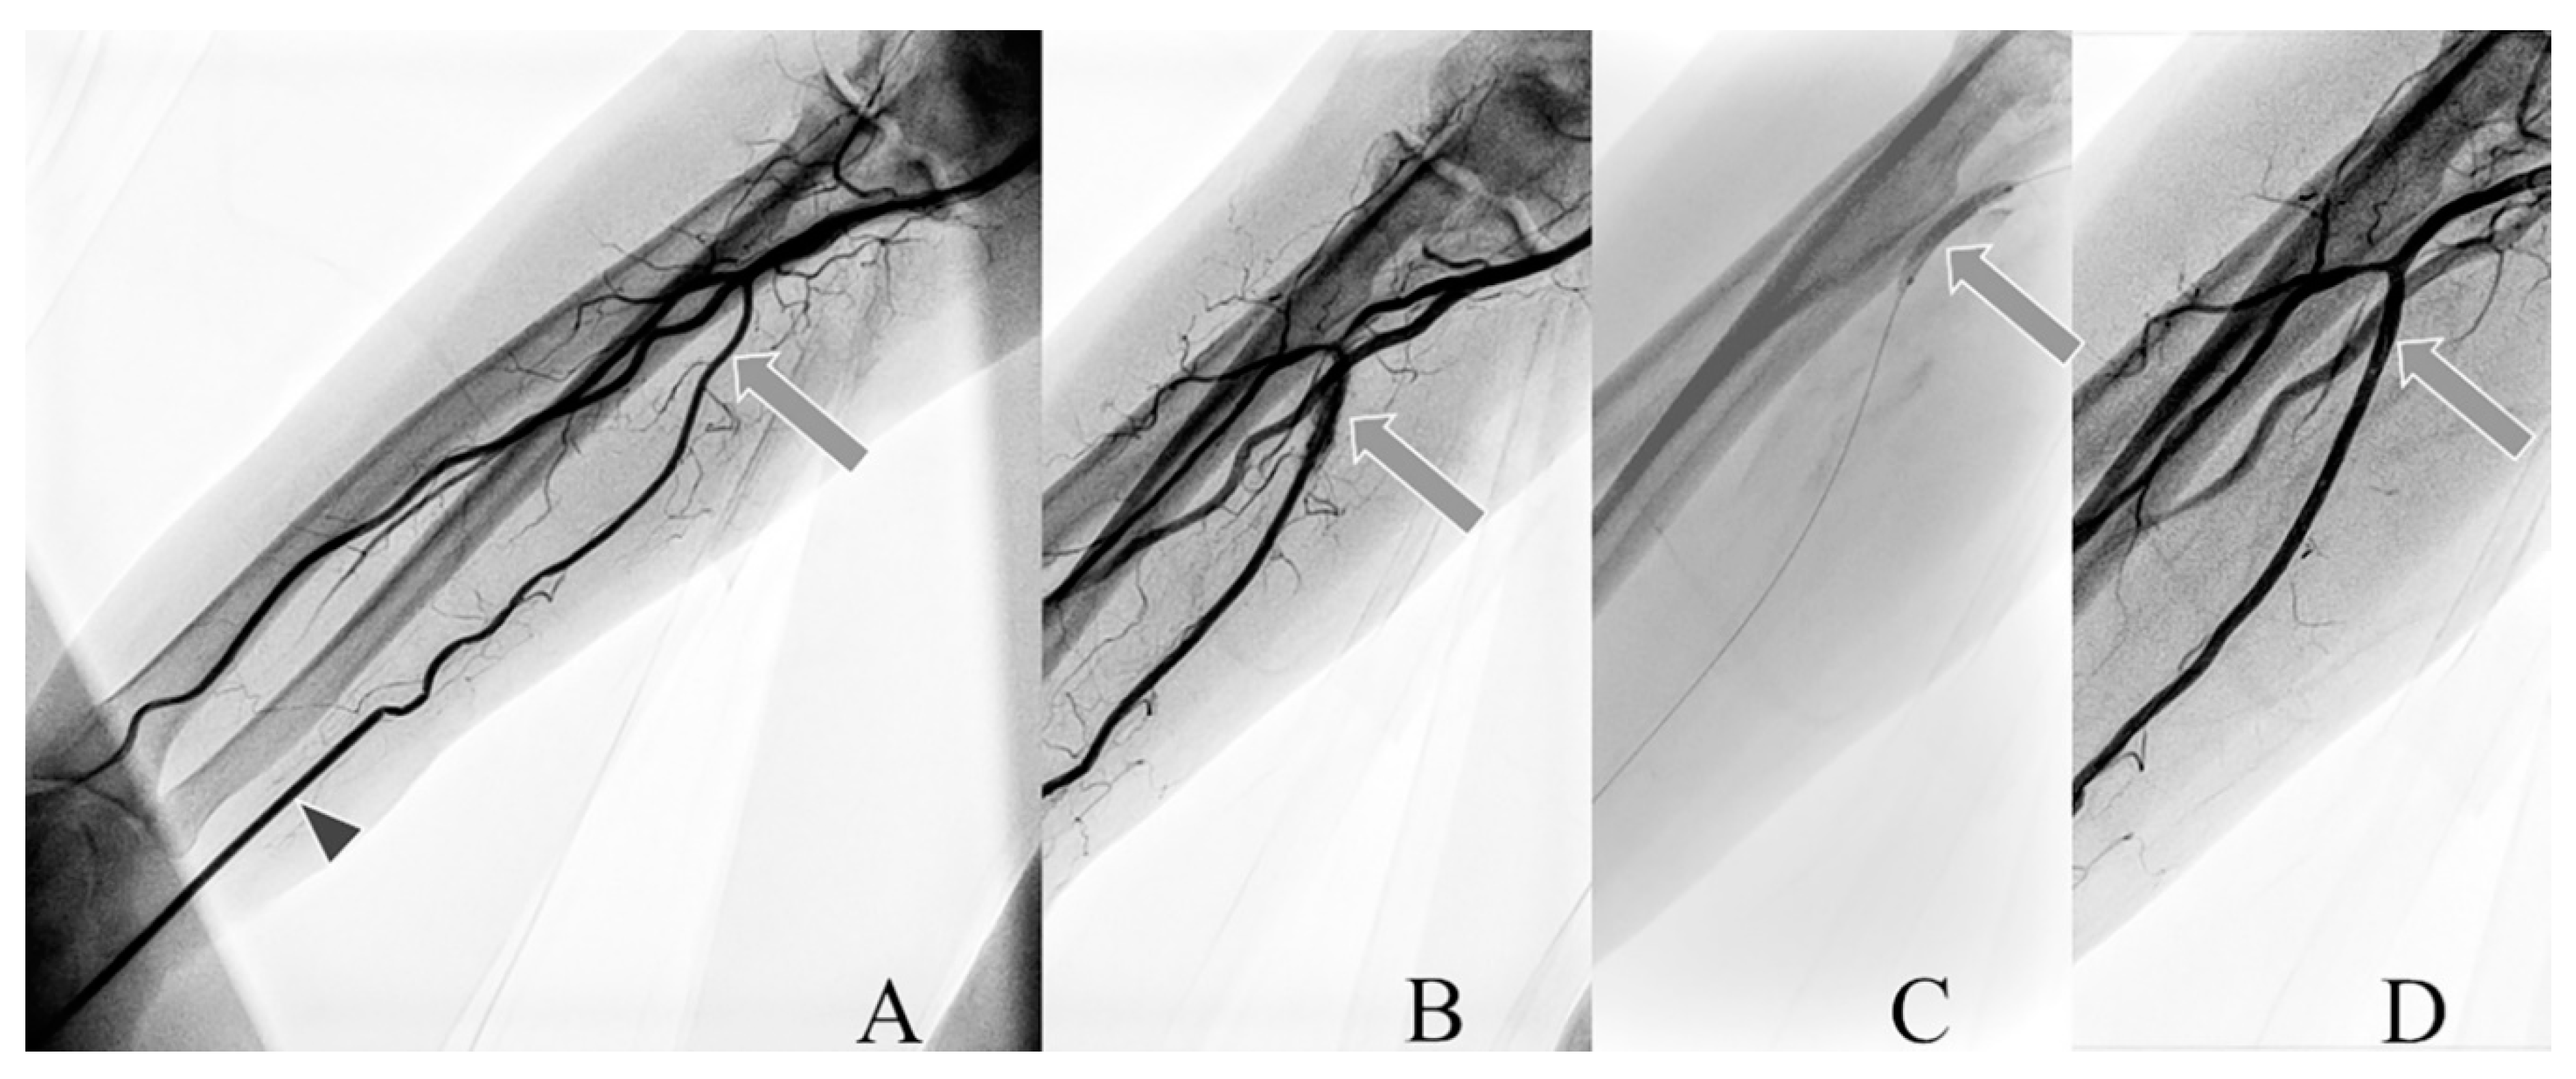

The average of two measurements of crossectional diam. (perpendicular to each other) was calculated. Measurement of the internal artery diam. was performed at the wrist level (1st diam.), at half of the length of the forearm (2nd diam.), and below the elbow (3rd diam.). The index of artery domination (IxD) was determined by the average of the levels of forearm measurements (Figure 1).

Figure 1. Diagram of radial artery diam. measurements. (A) elbow level, (B) ½ half forearm level, (C) wrist level, crossing arrows in (A)—scheme of measurements of diam. in the transverse projection of the radial artery.